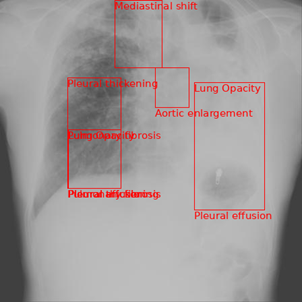

Figure 4 shows an example with many abnormalities and multiple global labels. The model accurately predicts ’Pneumonia’ and ’Other disease’, but hallucinates an additional global label of ’Tuberculosis’. The model accurately predicts some of the local abnormalities with great accuracy such as the mediastinal shift at the top and pleural effusion on the right lung. Apart from this, the model does hallucinate pleural thickening and pulmonary fibrosis in the left lung and aortic enlargement while missing the infiltration and pneumothorax. Despite this, the model performs well for this more ”difficult” data point.

Refer to caption

(a) Pneumonia, Other diseases (Test Labels)

(b) Pneumonia, Tuberculosis, Other diseases (Model Outputs)

Figure 4. Qualitative comparison between test labels and model output for multiple abnormalities.